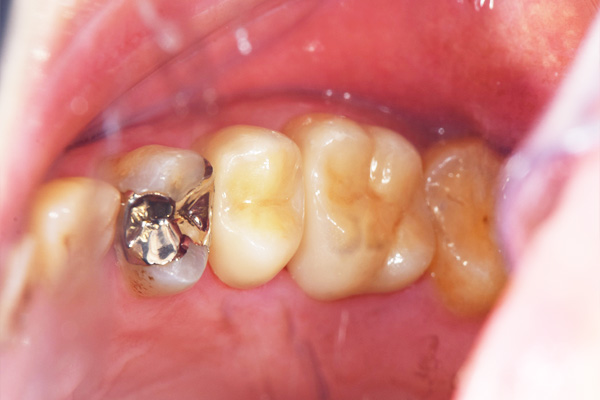

インレーの症例

インレー症例

治療前

途中経過

治療後

年齢・性別 43代・女性

主訴 パラジウムインレー2次カリエスの治療

治療内容 左上6セラミックインレー・

左上7ゴールドインレー

治療期間 10日程度

リスク・副作用 虫歯が深ければ、つけた後しみたり、痛みが出る可能性がある。 その場合は神経をとる処置をする。

歯ぎしり、くいしばりでセラミックインレーが割れることがある。

費用 セラミックインレー 55,000円

ゴールドインレー 88,000円